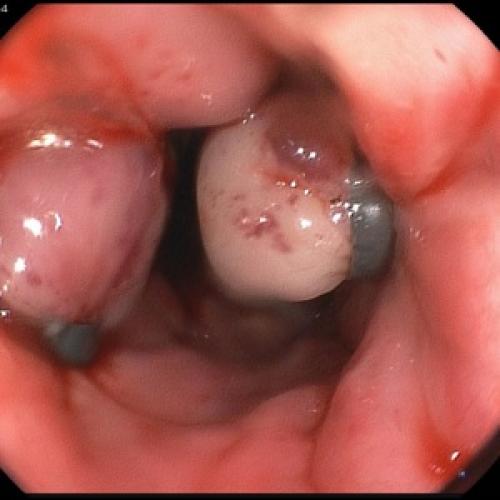

Пациентам с предположительным клиническим диагнозом острого панкреатита показано выполнение ЭГДС (дифференциальный диагноз с язвенным поражением гастродуоденальной зоны, осмотр БДС).

Отсутствие эффекта от проводимой анальгетической и спазмолитической терапии в течение 12-48 часов, быстро прогрессирующая желтуха, отсутствие желчи в ДПК при ЭГДС, признаки билиарной гипертензии по данным УЗИ свидетельствуют о стеноза терминального отдела холедоха (вклиненный конкремент БДС, папиллит). В этом случае показано проведение ЭПСТ. При остром панкреатите ЭПСТ производится без ЭРХПГ!

- ЭФГДС